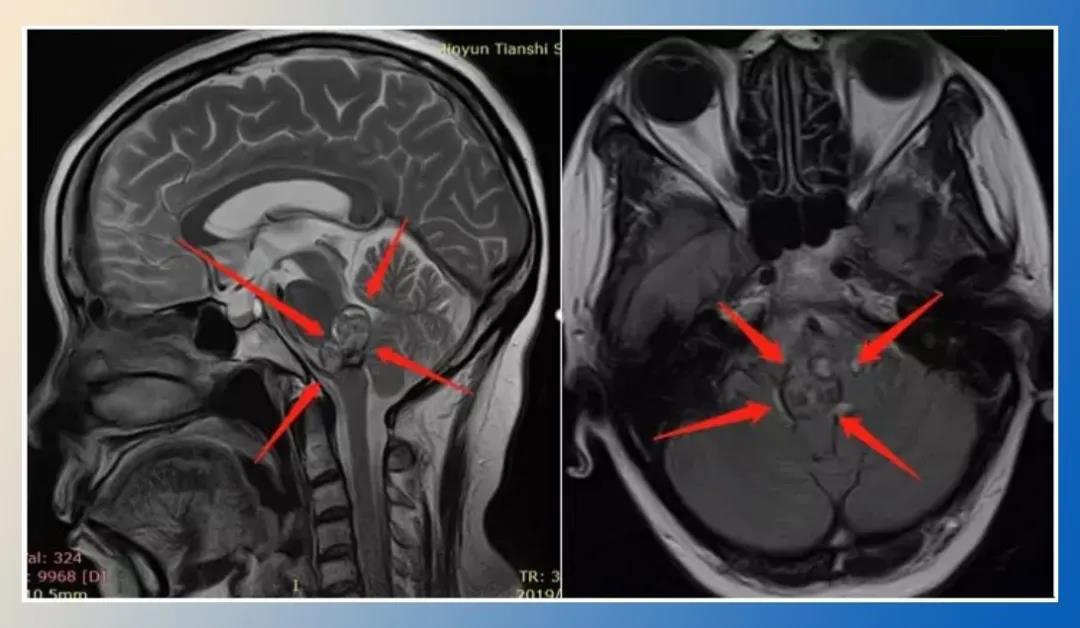

1、术前诊断:脑干脑桥海绵状血管瘤,6次脑干出血活动期,压迫四脑室

术后48小时内MR复查显示肿瘤全切